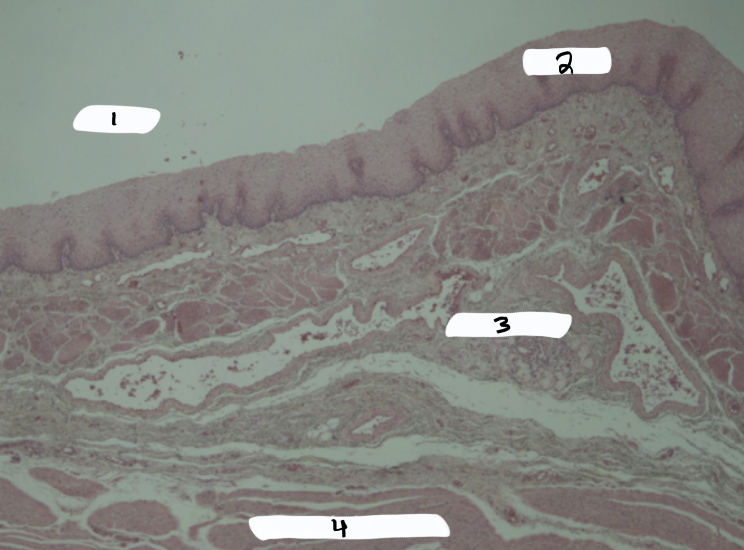

appendix

what is this a sample of?

submucosa

what is #1?

mucosa

what is #2?

lumen

what is #3?

serosa

what is #4?

muscularis externa

what is #5?